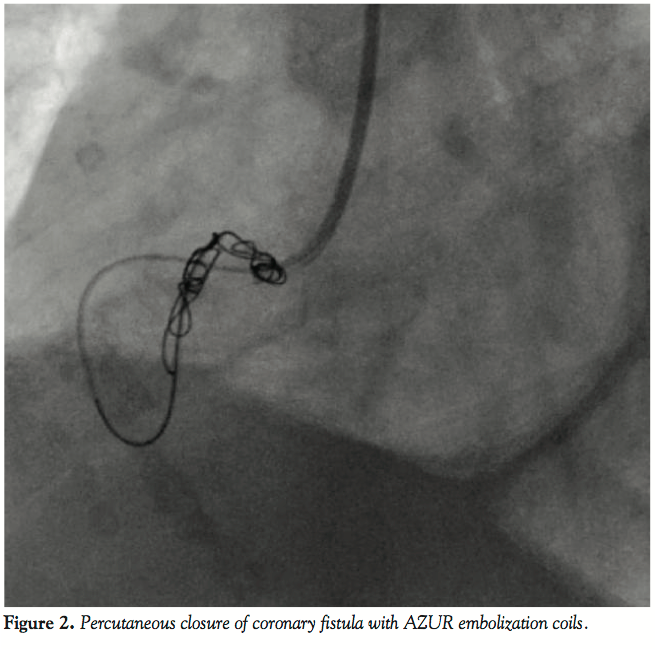

A coronary angiogram showed no signs of atherosclerotic coronary artery disease. However, it revealed a voluminous fistula between the proximal segment of the right coronary artery and a branch of the pulmonary artery. Without other plausible causes for her condition, the patient was subsequently called for percutaneous closure of the coronary fistula, which was successfully performed using 3 AZUR embolization coils (platinum coils coated with hydrocolloid gel). Figures 1-3 show the coronary fistula before, during, and after the procedure. One month later, she is asymptomatic.

Although successful fistula occlusion has been reported with inflatable and detachable balloons,17-19 percutaneous embolization technique with micro-particles of polyvinyl alcohol foam,20,21 and with umbrellas,22 the use of implantable coils is currently considered the preferential method due to improved control and delivery techniques, higher success rate, and lower risk of complications.23 Stainless steel coils,24 controlled-release coils (such as the Terumo detachable AZUR Peripheral HydroCoil Embolization System used in our case), controlled-release PDA coils, and the Amplatzer PDA occluder25 are potential options. The most frequent complication associated with catheter-based closure is embolization of the occlusion device (occurring in 7 out of 40 patients described by Qureshi et al23).